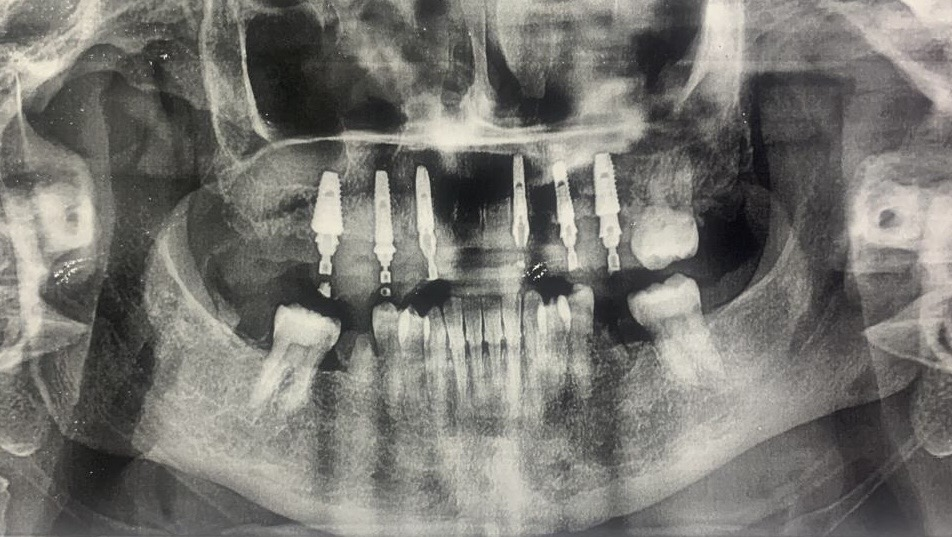

During the implant surgery, the dentist placed five implants in the maxillary arch and captured the precise implant positions using the Aoralscan Elite. Facial data were simultaneously recorded using the MetiSmile system. With this information, the dental technicians were able to design the prosthesis with enhanced accuracy.

The final prosthesis was delivered to the patient six months after surgery. The fitting process was smooth, and the patient expressed high satisfaction with the outcome. At the six-month follow-up, clinical examination confirmed the stability of both the prosthesis and the implants.

Fig. 39: 6 months follow up